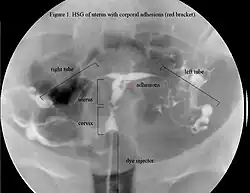

HSG showing filling defects at the adhesion sites. Additionally, this uterus appears to be T-shaped.

The history of a pregnancy event followed by a D&C leading to secondary amenorrhea or hypomenorrhea is typical. Hysteroscopy is the gold standard for diagnosis.[18] Imaging by sonohysterography or hysterosalpingography will reveal the extent of the scar formation. Ultrasound is not a reliable method of diagnosing Asherman's Syndrome. Hormone studies show normal levels consistent with reproductive function.